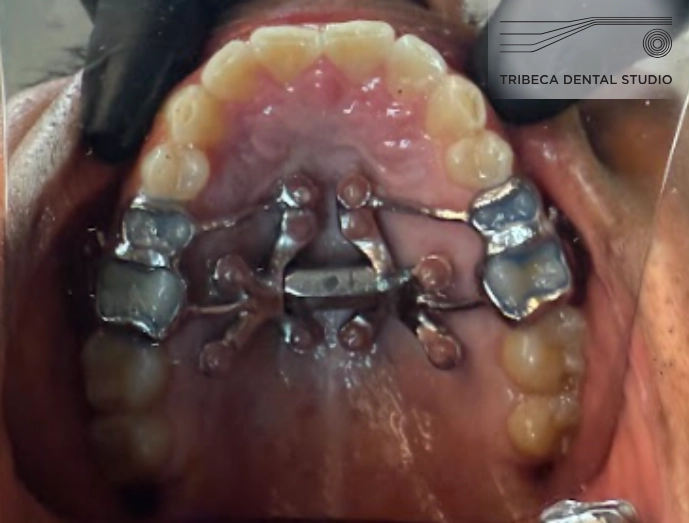

MARPE, on the other hand, is innovative because it makes palatal expansion available to adults by directly connecting the expander to the palatal bone. Dr. Reem specializes in a type of MARPE called MSE, which creates a parallel expansion rather than the typical V-shaped expansion that other MARPE methods offer. MSE and other MARPE treatments have helped many of her patients live more carefree lives.

3. On the day of your appointment, Dr. Reem will place a small piece of hardware similar to a retainer on the roof of your mouth. She fixes it to the palate with micro-screws (and proper pain management, of course).

4. You will return home with a key that you’ll connect to the MARPE hardware and turn at regular intervals.

5. This slowly creates outward pressure on your palate and expands it. Eventually, you’ll hear a pop when the two halves of the palate separate. No worries! That means it’s working.

6. Once you’ve done the prescribed amount of key turning, you’ll passively wear the MARPE hardware for a few months until the bone regenerates and heals in its new, more spacious shape.